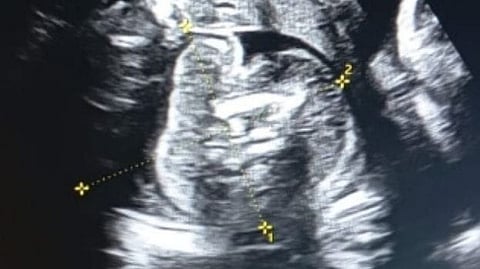

नऊ महिन्यांची गर्भवती असलेल्या महिलेच्या पोटातील गर्भाच्या पोटातही गर्भ वाढत असल्याचे नैसर्गिक आश्चर्य सोनोग्राफी तपासणी दरम्यान आढळून आले आहे. बुलढाणा जिल्हा सामान्य रुग्णालयात दोन दिवसांपूर्वी, दोन आपत्यांची माता असलेली (३२ वर्षीय) गर्भवती महिला सोनोग्राफी तपासणी करवून घेण्यासाठी आली होती. रुग्णालयातील डॉ.प्रसाद अग्रवाल यांना महिलेच्या सोनोग्राफी तपासणी दरम्यान दुर्मिळातील दुर्मिळ प्रकार दिसून आला. महिलेच्या पोटातील नऊ महिन्यांच्या गर्भाच्या पोटात आणखी एक गर्भ वाढत असल्याचे प्रथमच त्यांना दिसून आले. त्यामुळे डॉ.अग्रवाल आश्चर्यचकित झाले.

गर्भाच्या पोटात गर्भ आढळण्याचा हा प्रकार प्रसुतीबाबत गुंतागुंतीचा व जोखमीचा राहण्याची संभावना असल्याने डॉ.अग्रवाल यांनी या सोनोग्राफी रिपोर्ट बाबत जिल्हा शल्यचिकित्सक डॉ.भागवत भुसारी, शासकीय वैद्यकीय महाविद्यालयाचे अधिष्ठाता डॉ .झिने व महिला रुग्णालयाचे अधीक्षक डॉ.पाटील यांनाही अवगत केले. या वरिष्ठ वैद्यकीय तज्ञांच्या मार्गदर्शनाखाली सदर महिलेची पुन: सोनोग्राफी तपासणी करण्यात आली. नऊ महिन्याच्या गर्भाची पुर्ण वाढ झालेली आहे, मात्र त्या गर्भाच्या पोटातील गर्भाची वाढ झालेली नाही.

आज बुलढाणा येथील आमच्या यूएसजी क्लिनिकमध्ये आढळून आलेली केस ही दुर्मिळ अशी आहे. पाच लाख गर्भवती महिलांमागे अशी एक 'केस' आढळून येऊ शकते. त्याला FETUS in FeTO असे म्हटले जाते. आतापर्यंत अशा केवळ २०० केसेस नोंदवल्या गेल्या आहेत, तेही बाळंतपणानंतर (भारतात आजपर्यंत १० ते १५ केसेस नोंद झाल्या आहेत). मला गर्भवती महिलेच्या पोटातील बाळामध्ये काहीतरी असामान्य दिसून आले. तो जवळजवळ ३५ आठवड्यांचा सामान्य वाढणारा गर्भ होता. त्याच्या पोटात काही हाडे आणि गर्भासारखी रचना होती. मला लगेच लक्षात आले की हे सामान्य नाही. ही जगातील सर्वात दुर्मिळ केसेसपैकी एक आहे.